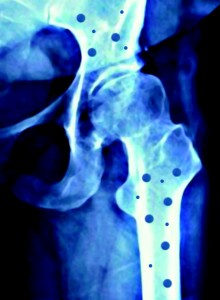

En nuestro país conviven 2,5 millones de mujeres mayores de 50 años con osteoporosis. Sin embargo, y como ha alertado el doctor Rafael Sánchez Borrego, presidente de la Asociación Española para el Estudio de la Menopausia (AEEM), miembro de Somos Pacientes, en el marco del XXXII Congreso Nacional de la Sociedad Española de Ginecología y Obstetricia (SEGO) celebrado en Santa Cruz de Tenerife, “hasta un 80% de las mujeres que presentan un alto riesgo de desarrollar osteoporosis o que ya han sufrido una fractura no han sido diagnosticadas o tratadas de la enfermedad”.

La población española, así como los profesionales sanitarios, son cada vez más conscientes de la importancia de la osteoporosis. Así, en los últimos años se ha producido un incremento del uso de las pruebas diagnósticas –por lo general, densitometrías óseas– para su detección. Pruebas que han detectado que la osteopenia –esto es, la pérdida de masa ósea que constituye la antesala de la osteoporosis– afecta cada vez a mujeres más jóvenes, sobre todo entre los 30 y los 40 años.